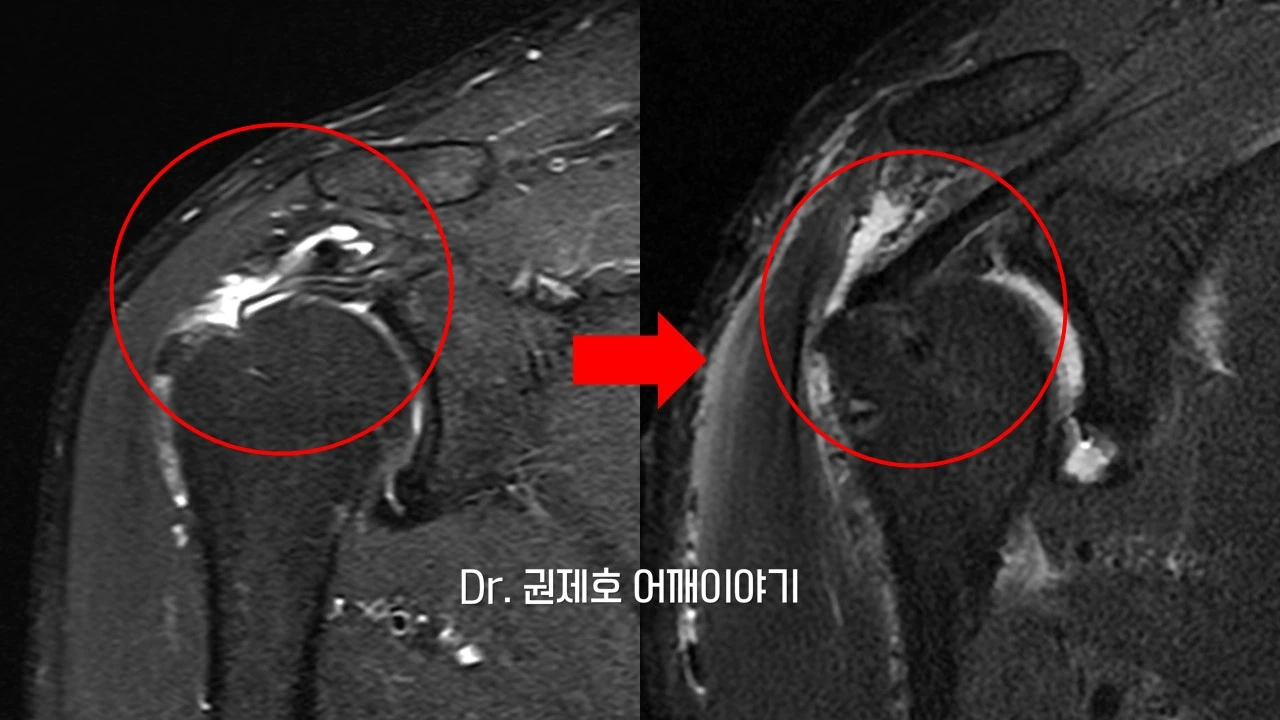

하루 이틀 지나서 어느 정도 수술에 대한 통증이 완화가 되면 MRI를 다시 검사하여 회전근개봉합수술의 결과를 판단한다. 말렸던 인대가 잘 당겨져 와서 뼈에 튼튼하게 고정된 모습을 알 수 있다.

첫 검사와 어깨 관절경 후를 비교하면 회전근개봉합수술의 결과를 보다 정확하게 알 수 있다. 말렸던 인대가 다시 뼈에 당겨져서 붙은 모습이다.